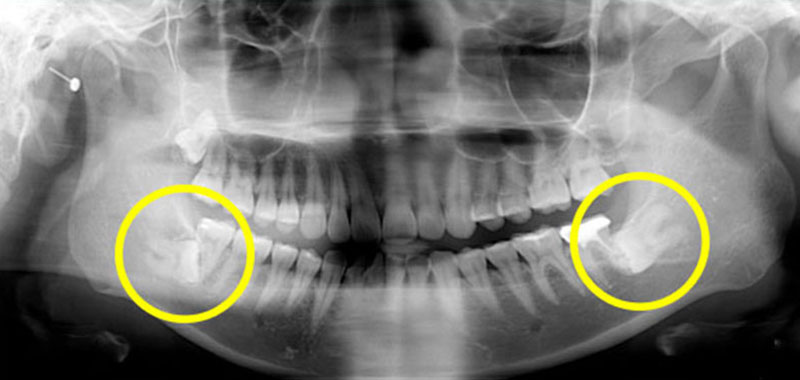

兩側下顎深埋在骨頭裡的水平智齒,右邊上顎智齒也深埋在骨頭內長不出來!這樣的智齒如果沒有症狀不一定要拔